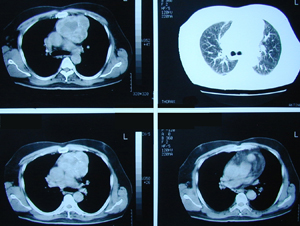

Εικόνα 3 α-δ

Αξονική τομογραφία του θώρακος. Επιβεβαιώνει τα ευρήματα της ακτινογραφίας του θώρακος. Δείχνει μάζα μαλακών μορίων, με νεκρώσεις, στο οπίσθιο μεσοθωράκιο χωρίς σημεία διήθησης παρακείμενων οργάνων.

A-B

Γ-Δ